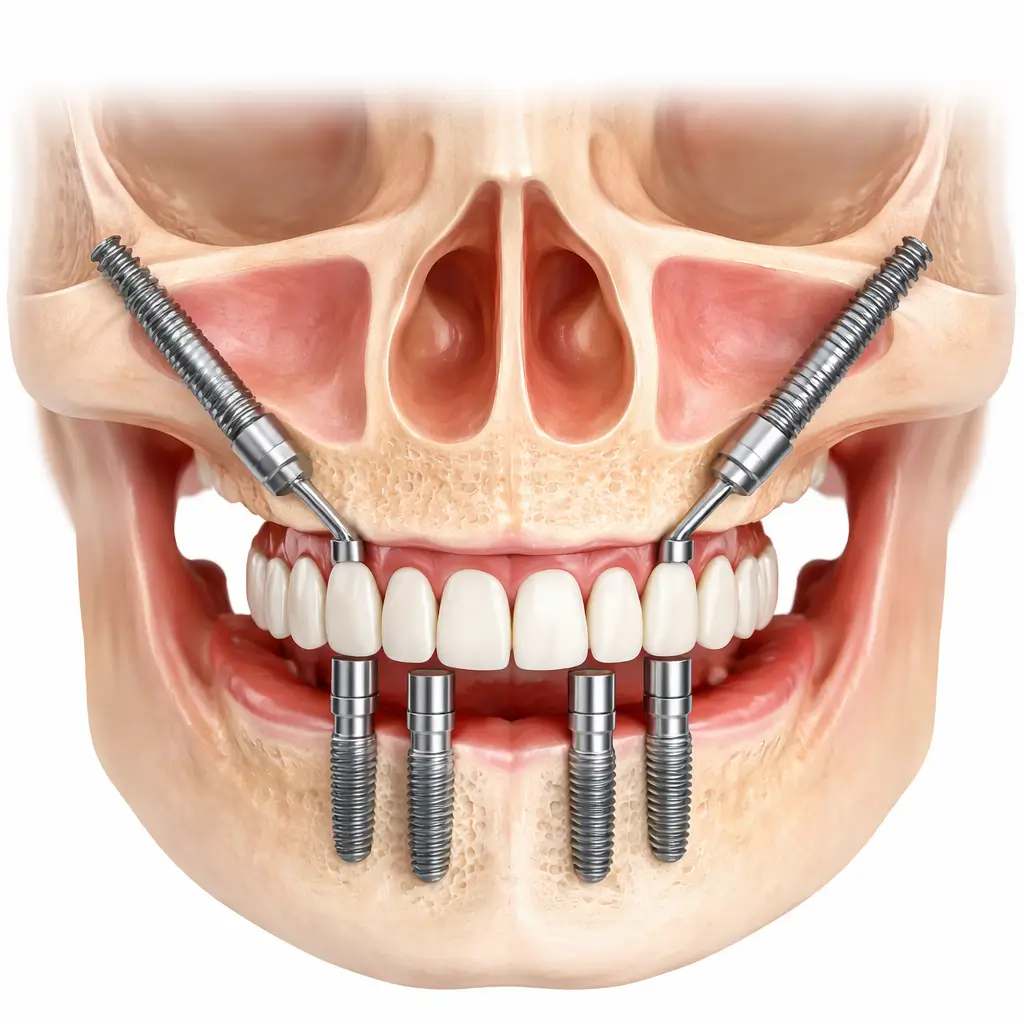

A dental implant is a sophisticated titanium post that acts as a prosthetic root for a missing tooth. It is surgically placed into the jawbone, where it undergoes “osseointegration,” essentially fusing with the bone to provide a stable foundation. This structure supports a custom-made crown, ensuring your replacement tooth looks, feels, and functions like a natural one.

All-on-4 or All-on-6

Full-arch restoration for patients who have lost all their teeth in the upper or lower jaw.

Zygomatic Implants

Specialized implants for patients with severe bone loss who cannot undergo traditional procedures.